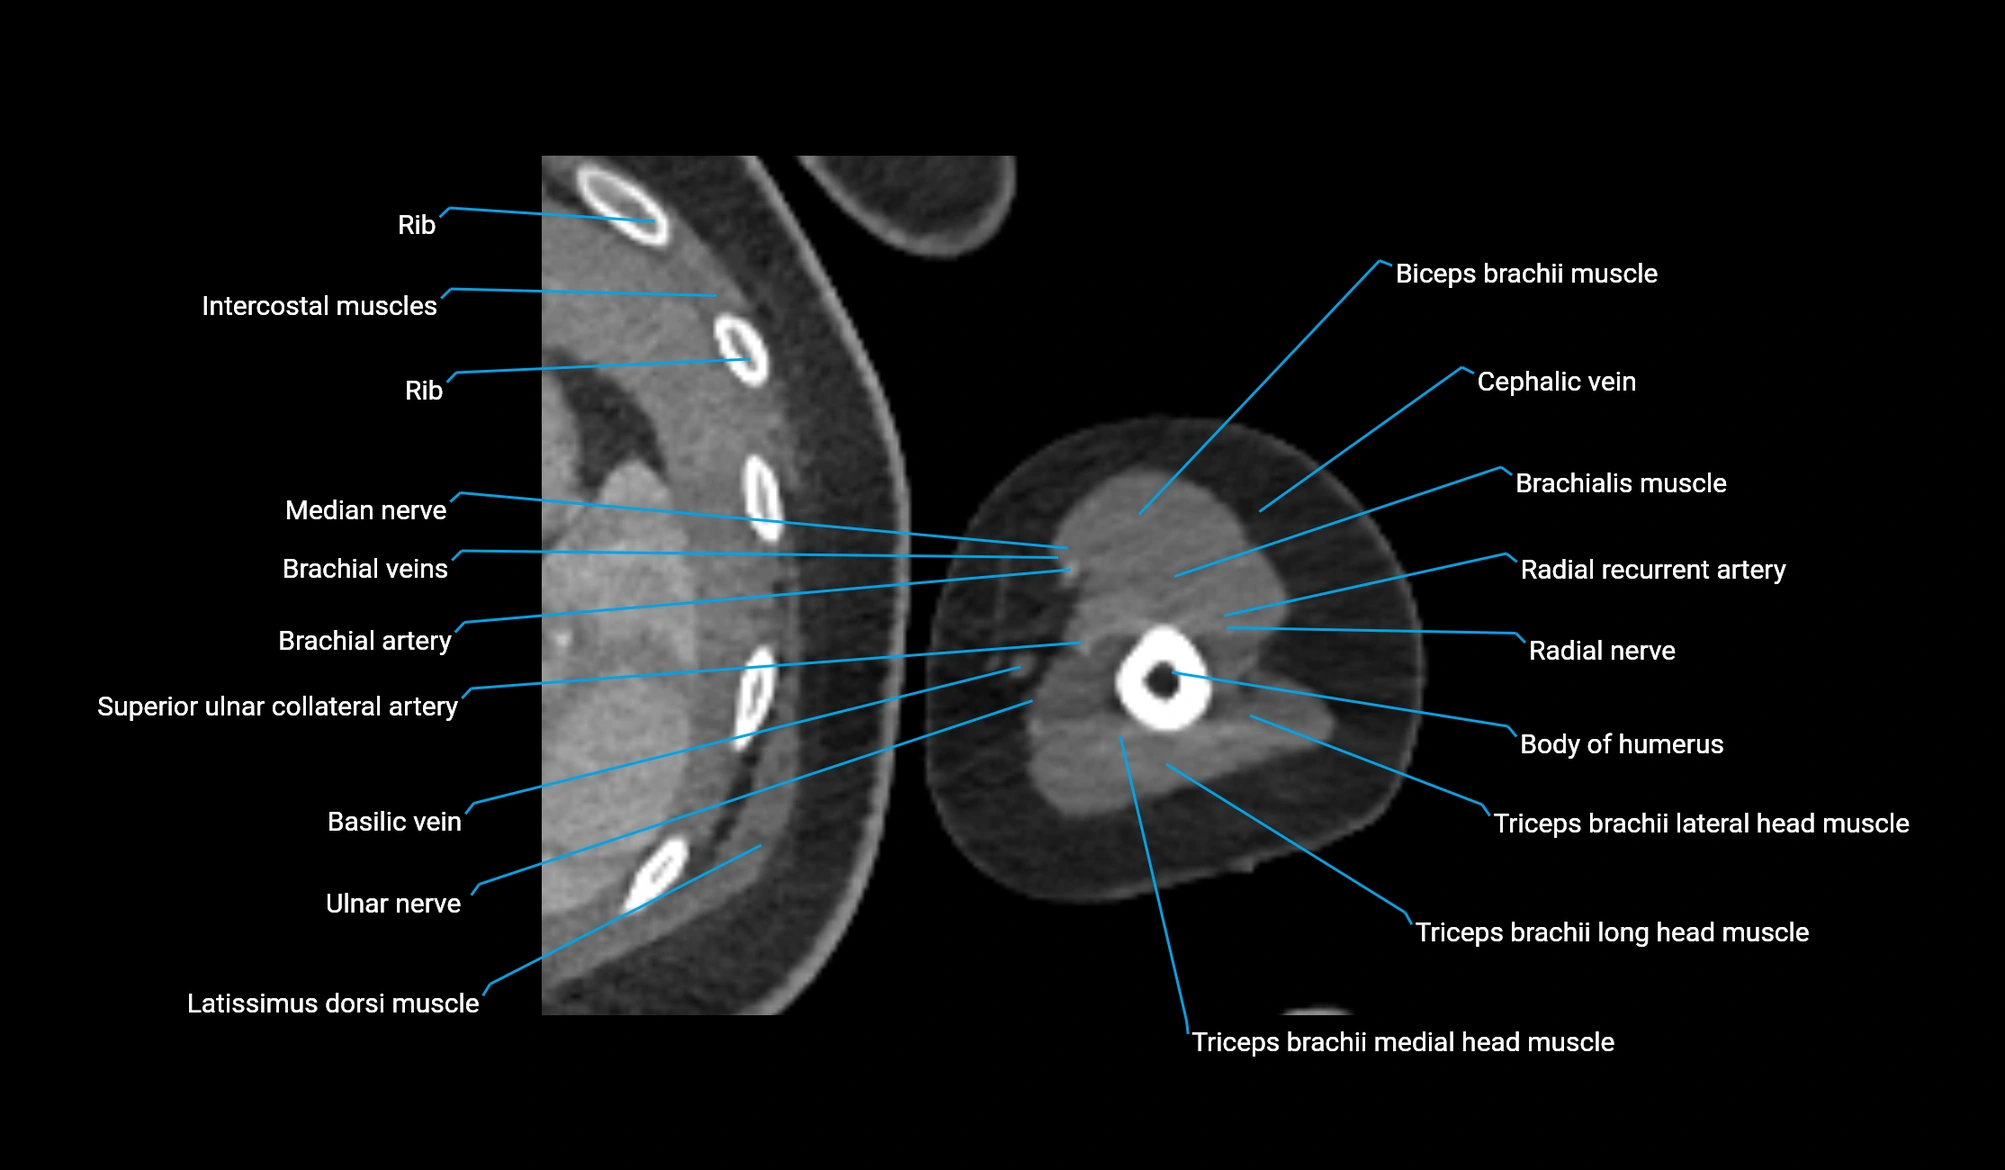

- Body of humerus

- Brachial artery

- Brachialis muscle

- Cephalic vein

- Deep brachial artery

- Lateral head of triceps brachii muscle

- Long head of triceps brachii muscle

- Medial head of triceps brachii muscle

- Median nerve

- Radial nerve

- Radial recurrent artery

- Superior ulnar collateral artery

- Ulnar nerve